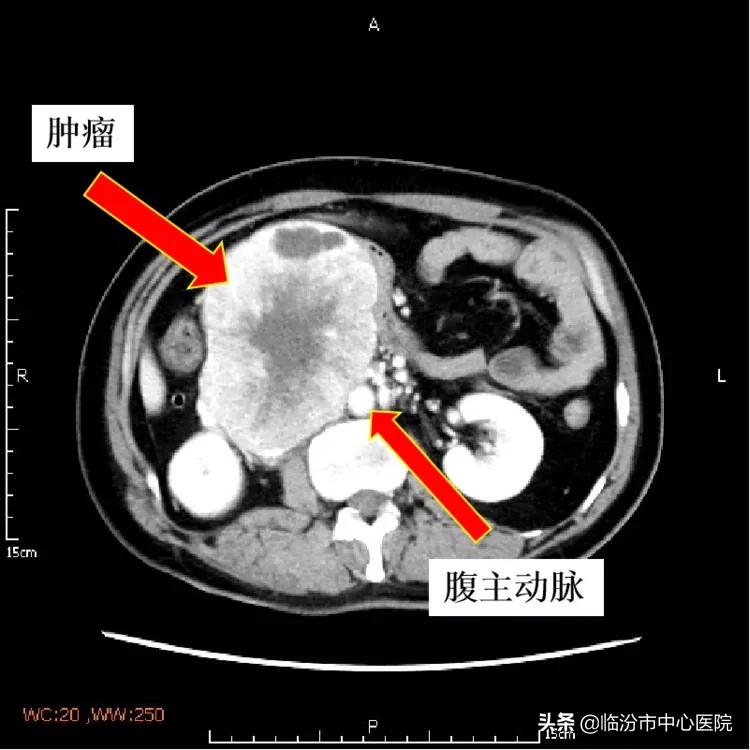

何女士来到市中心医院就诊后,行全腹盆CT检查发现肿瘤位于腹膜后方,体积较大,与腹主动脉、下腔静脉、右肾动脉等大血管关系密切,并且肿瘤的血供非常丰富,下腔静脉已经被巨大瘤体包裹移位,非常危险。

经过手术探查发现,肿瘤位于腹膜后,在腹主动脉与下腔静脉之间,与腹主动脉粘连,牵一发而动全身。下腔静脉被肿瘤包裹挤压,变形移位,在手术剥离中稍有不慎就会引起出血或坏死。

松解、剥离、切除……术中,普外肿瘤团队认真细致、配合默契、如履薄冰,凭借过硬的技术和娴熟的技巧,将肿瘤逐步剥离腹主动脉、下腔静脉的粘连后进行切除。最终,肿瘤被完整切除,重大血管完整保留,手术成功完成。

15cm*10cm*8cm的肿瘤完整切除